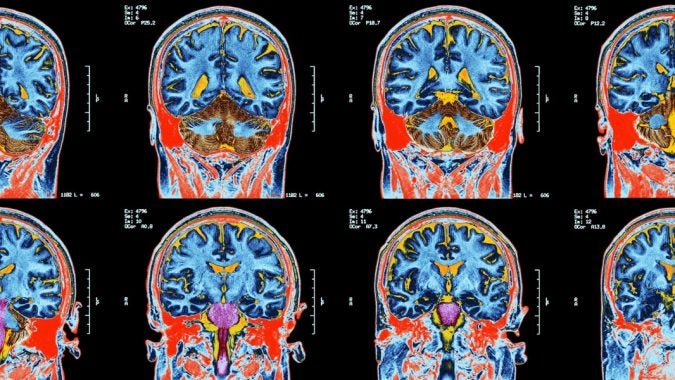

The First Lady of Boxing Won’t Let the Sport Ignore CTE

To ensure combat sports aren’t following the NFL’s very slow lead on head trauma, legendary manager Jackie Kallen is working on new technologies that will gauge the damage to boxers’ brains immediately after a fight

This Doctor Thinks He’s Found a Way to Treat CTE. So Why Won’t Anyone Fund His Research?

Earlier this summer, Dr. Charbel Moussa, director of the Georgetown University Laboratory for Dementia and Parkinsonism, presented a possible treatment for dementia and Parkinson’s at…